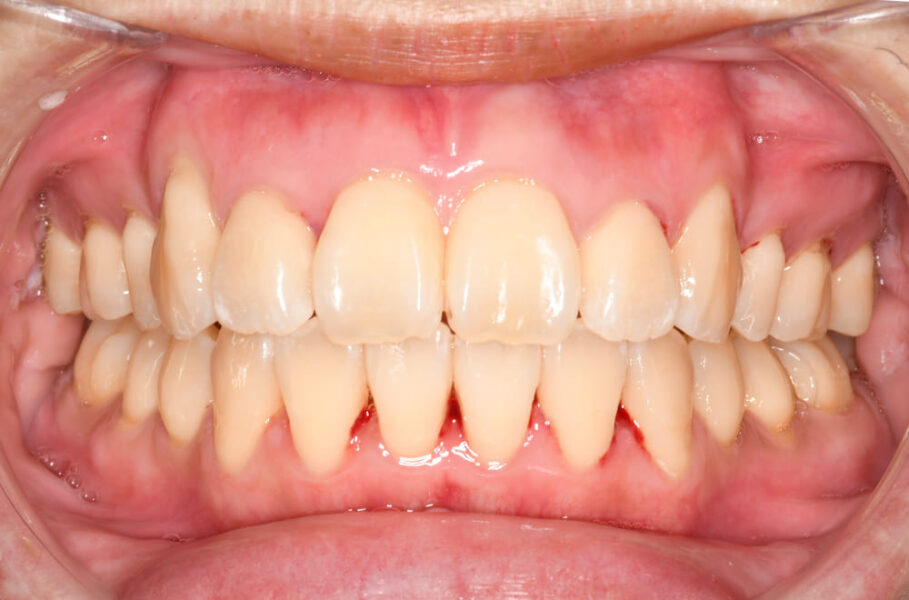

正面の口腔内写真では、矯正治療のみで重度の開咬が改善され、前歯部の上下的な重なりも平均的なオーバーバイト(2〜3mm)へと回復しました。

右側の写真でも、前歯部の唇側傾斜(出っ歯)の改善と安定した咬合関係が得られています。

また、前歯部の後退により口唇閉鎖不全も解消され、自然な口元となりました。

スマイル写真からも、治療後はより自然で調和の取れた笑顔を獲得でき、患者さまにも大変満足していただけました。

治療期間はおよそ2年で、術後のパノラマ写真では、歯根吸収もなく、良好な位置関係で歯列が安定しています。